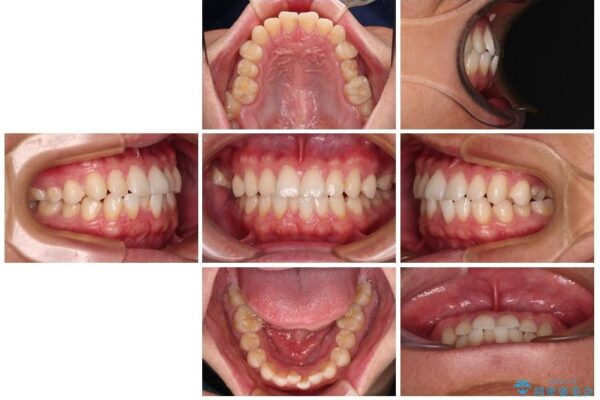

主訴:前歯のデコボコと奥歯のかみ合わせを治したい 今回ご紹介するのは、「前歯のガタガタ(叢生)」と「奥歯のかみ合わせ(シザーズバイト)」にお悩みでご来院された患者様の症例です。 患者様は、 ・歯並びをできるだけ早く改善したい ・費用を抑えた矯正治療 というご要望をお持ちでした。

・上顎左右の第二大臼歯が頬側へ転移し、シザーズバイト(scissors bite)の状態

・上顎左側第二小臼歯が90度捻転しており、噛み合わせに影響

治療前

• 前歯のガタガタ・奥歯のかみ合わせ(シザーズバイト)を改善|1年半で完了したメタルブラケット矯正 治療前画像